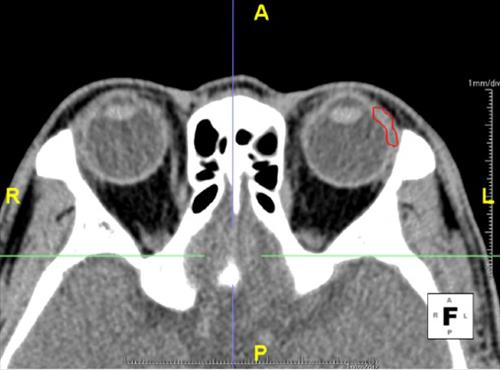

"'³ªÀ̵é¾î ´«¹°µµ ¸»¶ú´Ù'´Â ¸»Àº ÀÇÇÐÀûÀ¸·Î »ç½Ç" 109¸í ´«¹°»ù ºÎÇÇ ÃøÁ¤°á°ú, ³ªÀÌ µé¼ö·Ï ´«¹°»ù ºÎÇǰ¨¼Ò (¼¿ï=¿¬ÇÕ´º½º) ±è±æ¿ø ±âÀÚ = ³ëÀεéÀÌ ÈçÈ÷ ¸»ÇÏ´Â "³ªÀ̰¡ µå´Ï ´«¹°µµ ¸»¶ú´Ù"¶ó´Â Ç¥ÇöÀº...